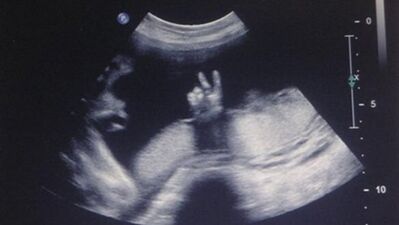

Bebekler anne karnında ne yapar?